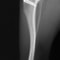

■ 症例20 ポメラニアン 8ヶ月 1.8kg

左右膝蓋骨脱臼 グレードⅢ

2ヶ月前から間欠的跛行が認められ、両膝の膝蓋骨脱臼整復術を行った。

手技は縫工筋及び内側広筋の解放、脛骨粗面の外側転位、滑車ブロック形造溝術、内外側関節包の縫縮を選択し実施した。

右側の膝蓋骨脱臼は上記手技で整復されたものの、左側はそれのみでは膝蓋骨が浮く様子が認められた。その為、PDS縫合糸にて膝蓋靱帯を1糸のみ縫合し、靱帯の縫縮を行った。

膝蓋骨脱臼は膝関節における膝蓋骨の内外側の脱臼と定義されるが、時として単純な内外の脱臼ではなく、膝蓋骨が大きく前方に浮き上がるように脱臼する場合がある。特にトイプードルやポメラニアンといった犬種に多く認められる。

内側脱臼に加えて前方への浮き上がりを矯正する為に、従来より脛骨粗面転移により膝蓋靭帯を外方と下方に引っ張り、固定する方法を選択する。膝蓋骨の前方への浮き上がりが軽度の場合は、従来法ではなく関節包の縫縮で対応していた。しかし、一部の症例で膝蓋骨の動きが悪くなり伸展機構が円滑に機能せずロボット様歩行になるケースがあった。

その為、膝蓋靭帯自体を縫縮する方法を採用した。この方法により、膝関節の伸展機構を妨げず膝蓋骨の軽度の浮きを矯正することが可能となった。

本症例の経過は良好である